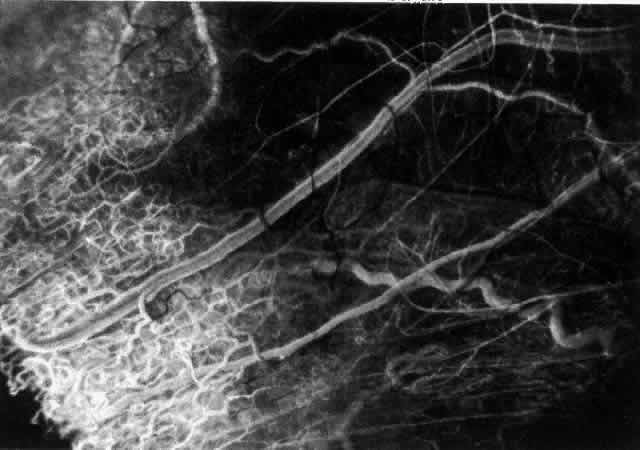

The characteristic features of necrotizing scleritis on fluorescein angiography are hypoperfusion and, eventually, nonperfusion of the vascular networks (Figs. 40 through 43).26 The initial changes are on the venous side of the capillary network; the transit time of the dye increases even if the eye is red and congested. If the disease process persists or has been present for a long time, thrombosis and permanent vaso-occlusive changes occur. These vessels (or the occluded capillary network) are bypassed by the opening of anastomotic channels. New vessels in a granuloma give rise to deep intrascleral leakage of dye (see Fig. 43). Conjunctival and episcleral involvement by the destructive change is late but is always preceded by vaso-occlusive changes that can sometimes be detected with use of the red-free light on the slit lamp (Figs. 44 and 45).